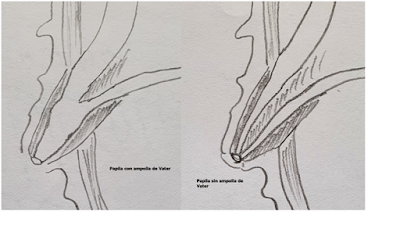

Las neoplasias mucinosas papilares intraductales (IPMN) son neoplasias epiteliales que crecen dentro del sistema de conductos del páncreas [1,2]. Las células neoplásicas suelen formar papilas y, a veces, producen grandes cantidades de mucina. Esta mucina y/o tejido tumoral papilar pueden distender localmente el sistema de conductos, produciendo así una lesión "quística".

Desde el punto de vista anatómico las IPMN se clasifican en 3 tipos, cada cual con un riesgo de malignidad ampliamente estudiado y conocido [3]:

IPMN de ducto principal: Que

corresponde a una dilatación segmentaria o difusa del CPP > 5 mm, sin otras

causas de obstrucción, con un riesgo de malignidad del 62.2%.

IPMN de rama lateral: Que

corresponde a un quiste pancreático > 5 mm que se comunica con el conducto

pancreático principal, con un riesgo de malignidad del 24.4%.

IPMN mixto: Que cumple con

criterios de los dos anteriores, con un riesgo de malignidad del 57.6%